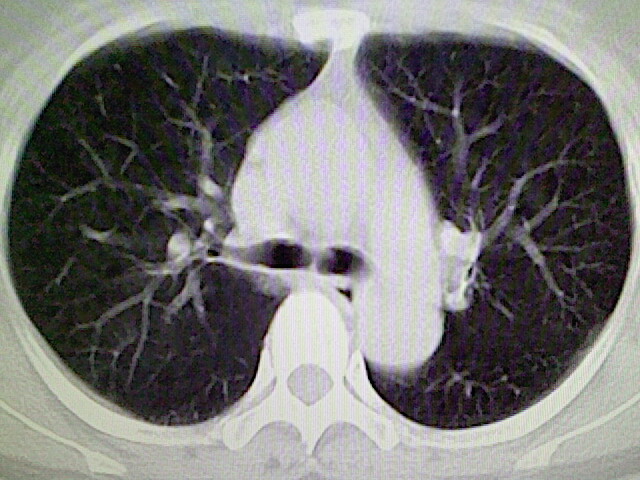

女,52岁,咳嗽,咳痰多日

左下肺陈旧纤维索条!

左肺舌段炎性改变

我见过几例,为炎症后纤维条索

慢性炎症后改变

考虑慢性炎性病灶粘连牵拉改变。

左肺舌叶纤维锁条病变。

左肺上叶下舌段炎症并局部胸膜反应。

左肺舌叶纤维索条影。

左肺舌叶段陈旧性病变

左肺舌段炎性反应。片子的质量太不好了。

左肺舌段炎性

炎性改变

左肺舌叶纤维索条影